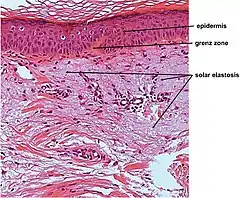

| Micrograph showing solar elastosis - grey, jumbled spaghetti-like material on bottom of image. H&E stain. | |

In the earlier stages of actinic elastosis, elastic fiber proliferation can be seen in the dermis. As the condition becomes more established, the collagen fibers of the papillary dermis and reticular dermis become increasingly replaced by thickened and curled fibers that form tangled masses and appear basophilic under routine haematoxylin and eosin staining. These fibers stain black with the Verhoeff stain.[2]